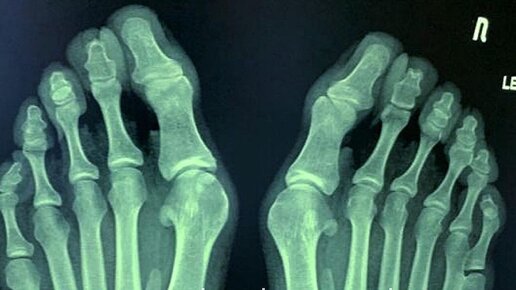

Больные суставы на пальцах рук, как правило, бывают не только в пожилом возрасте. Как уменьшить неудобство и боль? 5 действенных советов для тех, кто болеет артритом. Существует около двухсот видов артритов, основными причинами которых являются старение, воспаление, оседание кристаллов мочевой кислоты в суставах или инфекция. В каждом случае изменения могут быть разными. Иногда возникает только деформация, но часто болезнь сопровождается болью и нарушениями движений. Артрит имеет тенденцию поражать обе руки...